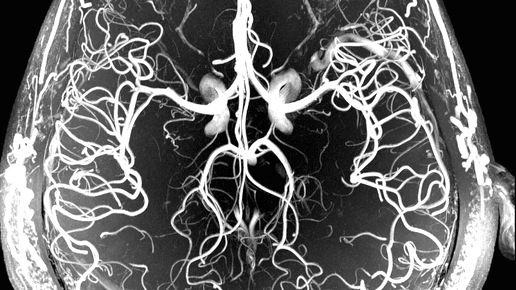

Омплексную МРТ головного мозга и сосудов головного мозга можно провести в любом МРТ центре Санкт-Петербурга. Обследование состоит из двух процедур: МР-ангиография; МРТ головного мозга. В процессе МРТ головного...